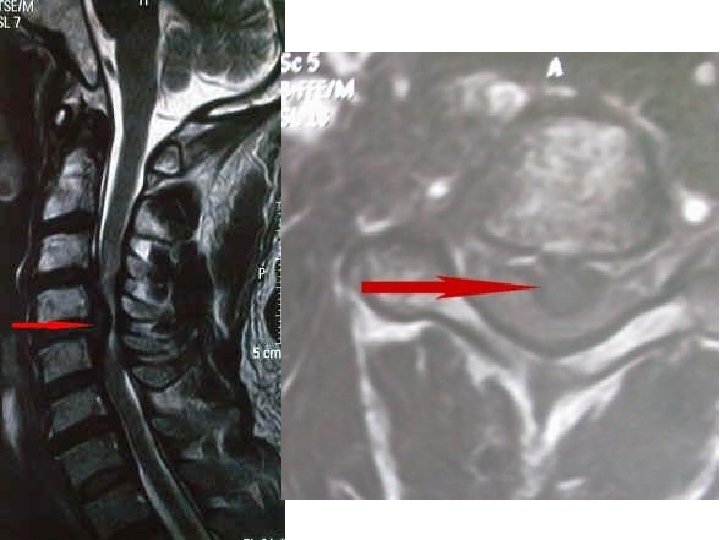

2. Neuropatski bol posledica oštećenja ili disfunkcije delova nervnog sistema (periferni i centralni) • poznatog uzroka • karakter žarenja, probadanja, sevanja, neugodnosti, znojenja, toplote, hladnoće • neurološki ispadi (senzorni ili motorni) • slab odgovor na NSAR

Periferni neuropatski bol • oštećenje perifernih živaca (tumor, hiruški zahvati, trauma, dijabetes, hemoterapija, radioterapija) • postherpetična neuralgija • neurolagija trigeminusa Centralni neuropatski bol • promene na mozgu i kičmenoj moždini (talamički bol kod moždanog udara, fantomski bol)